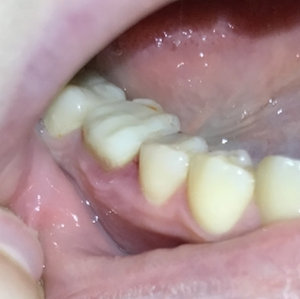

Доброго времени суток. Скажите пожалуйста: если болели зубы при накусывании в течение 2-х дней, болели не сильно, а потом прошли, то что это может быть? Спасибо.

Добрый день. В этом случае возможно на верхушках имеется воспаление. И оно, как правило, проявляется при снижении иммунитета. Я вам рекомендую обратится на очный прием к стоматологу-терапевту для составления плана лечения оперяясь на рентген снимки и на состояние зубов в полости рта. Запишитесь к нам на прием и мы обязательно вам поможем.